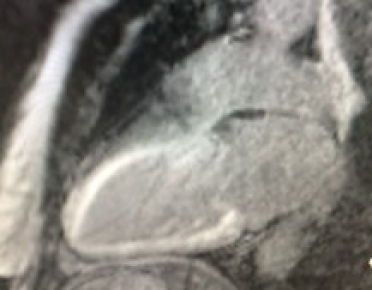

Cardiac magnetic resonance (CMR) imaging with gadolinium contrast can be useful in the identification of cardiac amyloidosis. Late gadolinium enhancement (LGE) occurs as contrast accumulates in the increased extracellular volume (ECV) secondary to amyloid deposition in the myocardium. LGE seen by CMR is one of the most accurate predictors of endomyocardial biopsy-positive amyloidosis [16]. There are a number of other CMR parameters that may be useful for the characterisation of myocardial tissue and possible infiltrative disease [17]. Recent data confirm the utility of the ECV value to assist in the diagnosis of CA [18]. CMR is a good early screening tool for cardiac amyloidosis and can be useful for detecting early fibrosis or infiltration prior to increasing LV thickness (Figure 2 A, B).

Figure 2. Common patterns of hyperenhancement on CMR potentially indicating cardiac amyloidosis. 2A. Diffuse hyperenhancement. 2B. Extensive subendocardial hyperenhancement on cardiac magnetic resonance imaging.

2A.